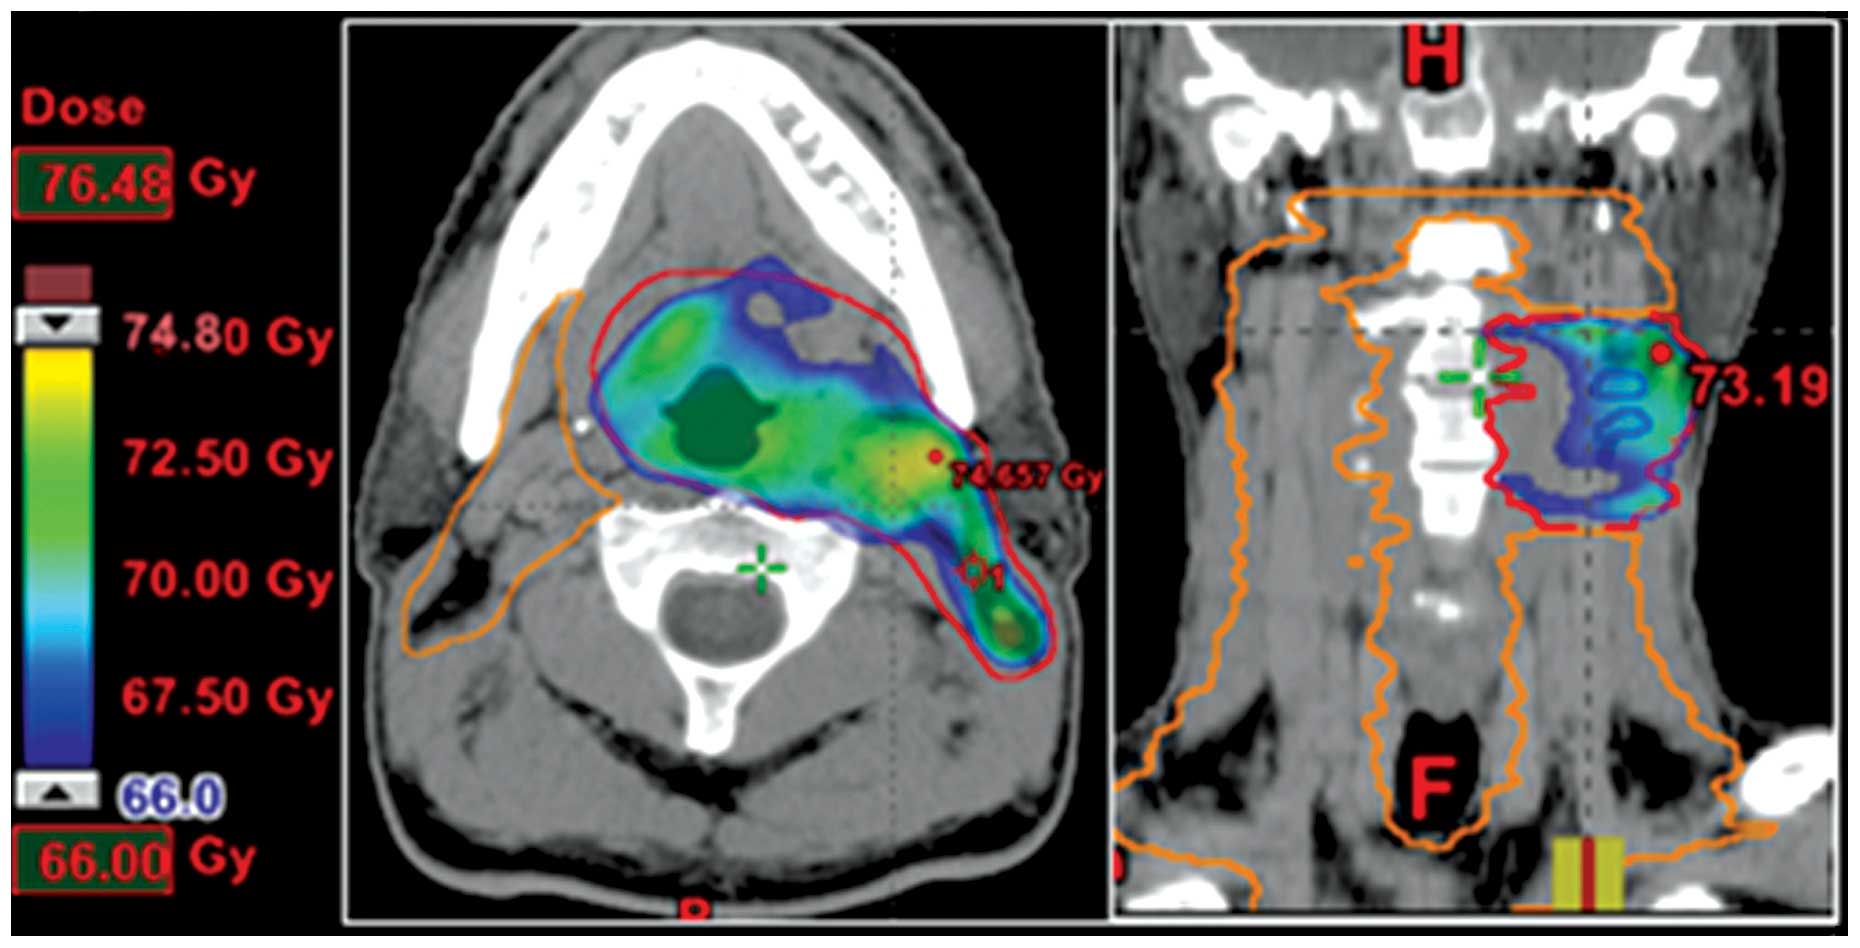

Dose Painting Imrt

Dose Painting Multicenter Phase Iii Trial In Newly Diagnosed